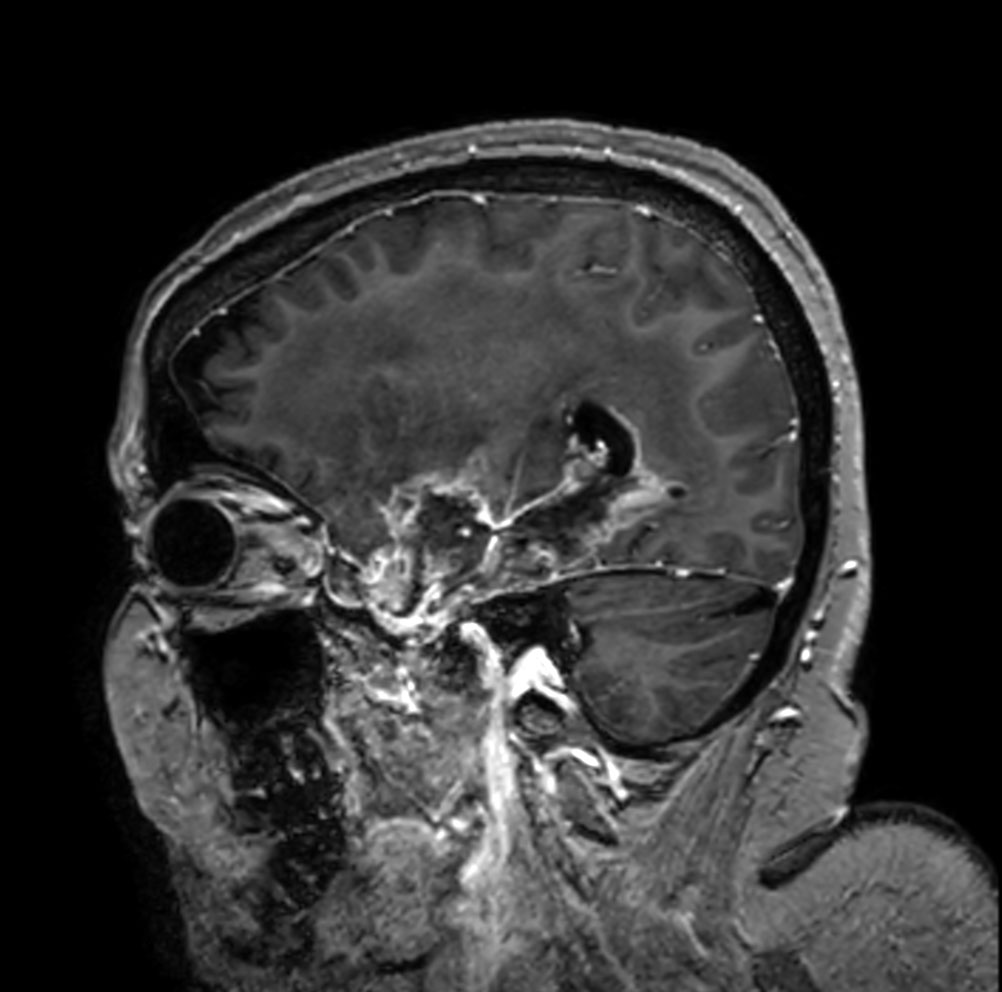

Sagittal T1w 3D TFE with gado

Patient with a history of astrocytoma. MRI scan requested post radiotherapy treatment. Diagnosis: Recurrent neoplastic disease.